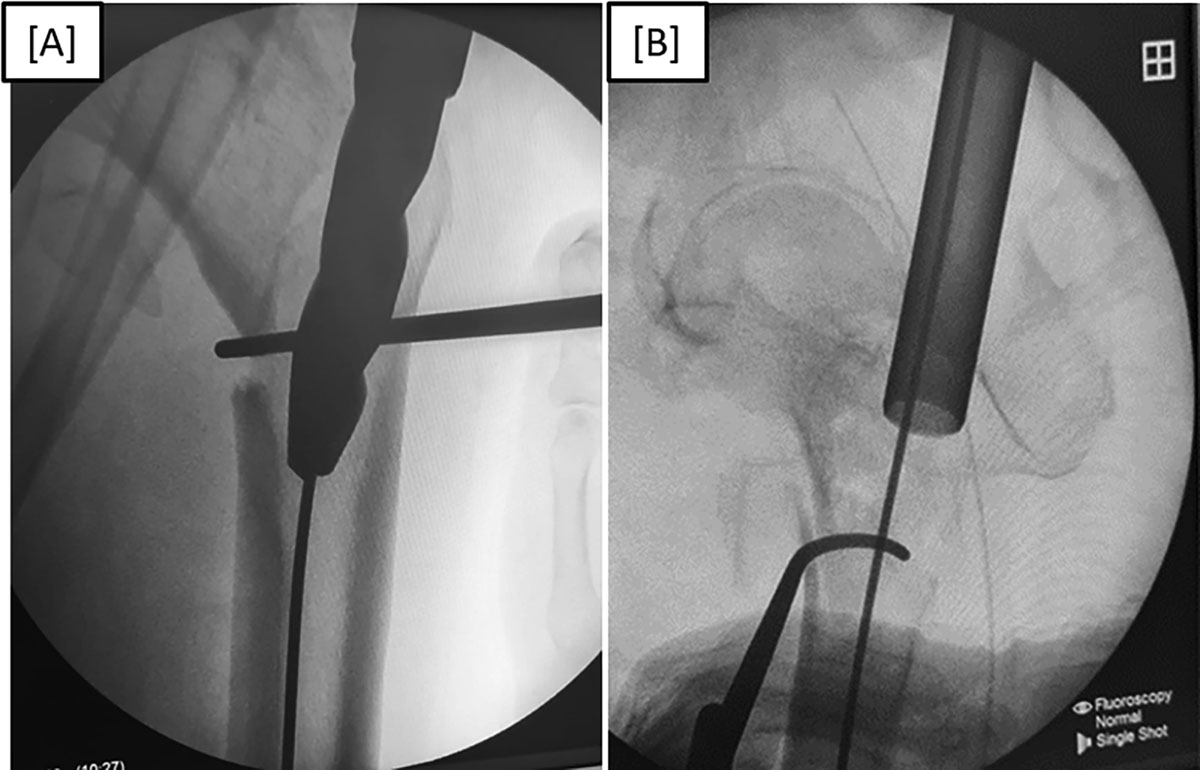

Figure 5

(A) Anteroposterior fluoroscopic view of left intertrochanteric fracture reduction using a bone hook during proximal femoral nail insertion. (B) Lateral fluoroscopic view of left intertrochanteric fracture reduction using a bone hook during proximal femoral nail insertion.